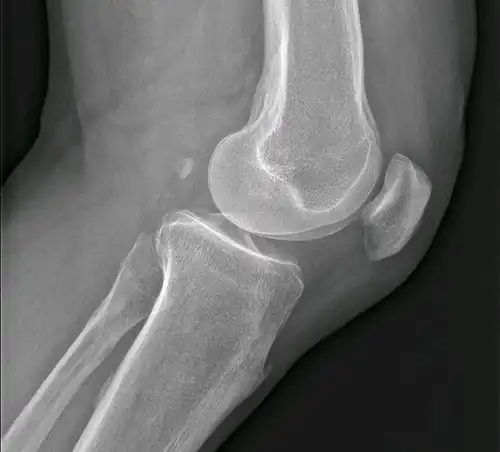

El suministro arterial y drenaje venoso de los diferentes órganos destaca en el estudio de las variaciones anatómicas por su importancia en la predisposición de varias patologías. A modo de ejemplo, resulta importante el conocimiento de las diferencias de dominancia de las arterias coronaria derecha e izquierda que irrigan el corazón por el mayor riesgo de muerte entre los que tienen dominancia de la arteria coronaria derecha.[4] Aparte de la irrigación, otras estructuras presentan variaciones del patrón común, pudiendo tener estas alteraciones importancia clínica el algún momento de la vida del individuo. Así, los músculos accesorios son duplicados anatómicos raros que ocurren ocasionalmente y solo requieren tratamiento cuando se altera la función. Un ejemplo lo encontramos con el músculo sóleo accesorio en el tobillo que, por lo general, no necesita ser rectificado.[16][17] Otras variaciones más comunes son la existencia de órganos internos accesorios como resultado de anomalías durante el desarrollo embrionario, como por ejemplo la existencia de un bazo accesorio, que se encuentra en alrededor del diez por ciento de la población y que ocasionalmente puede verse afectado por patologías particulares que son necesarias identificar.[18][19]